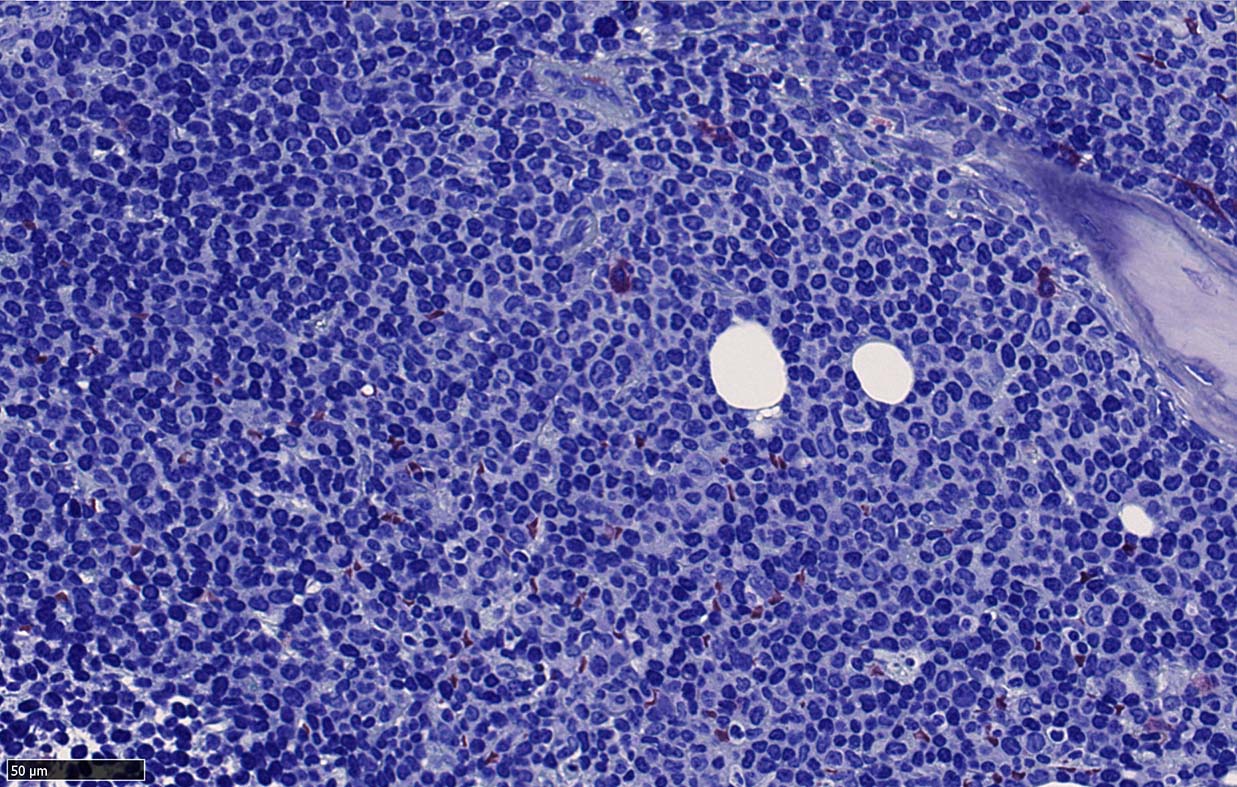

Bone marrow involvement of mantle cell lymphomaの症例

骨髄骨梁間に密なASD-Giemsa陰性の小型~中型円形細胞の浸潤が認められる.

骨髄浸潤細胞所見